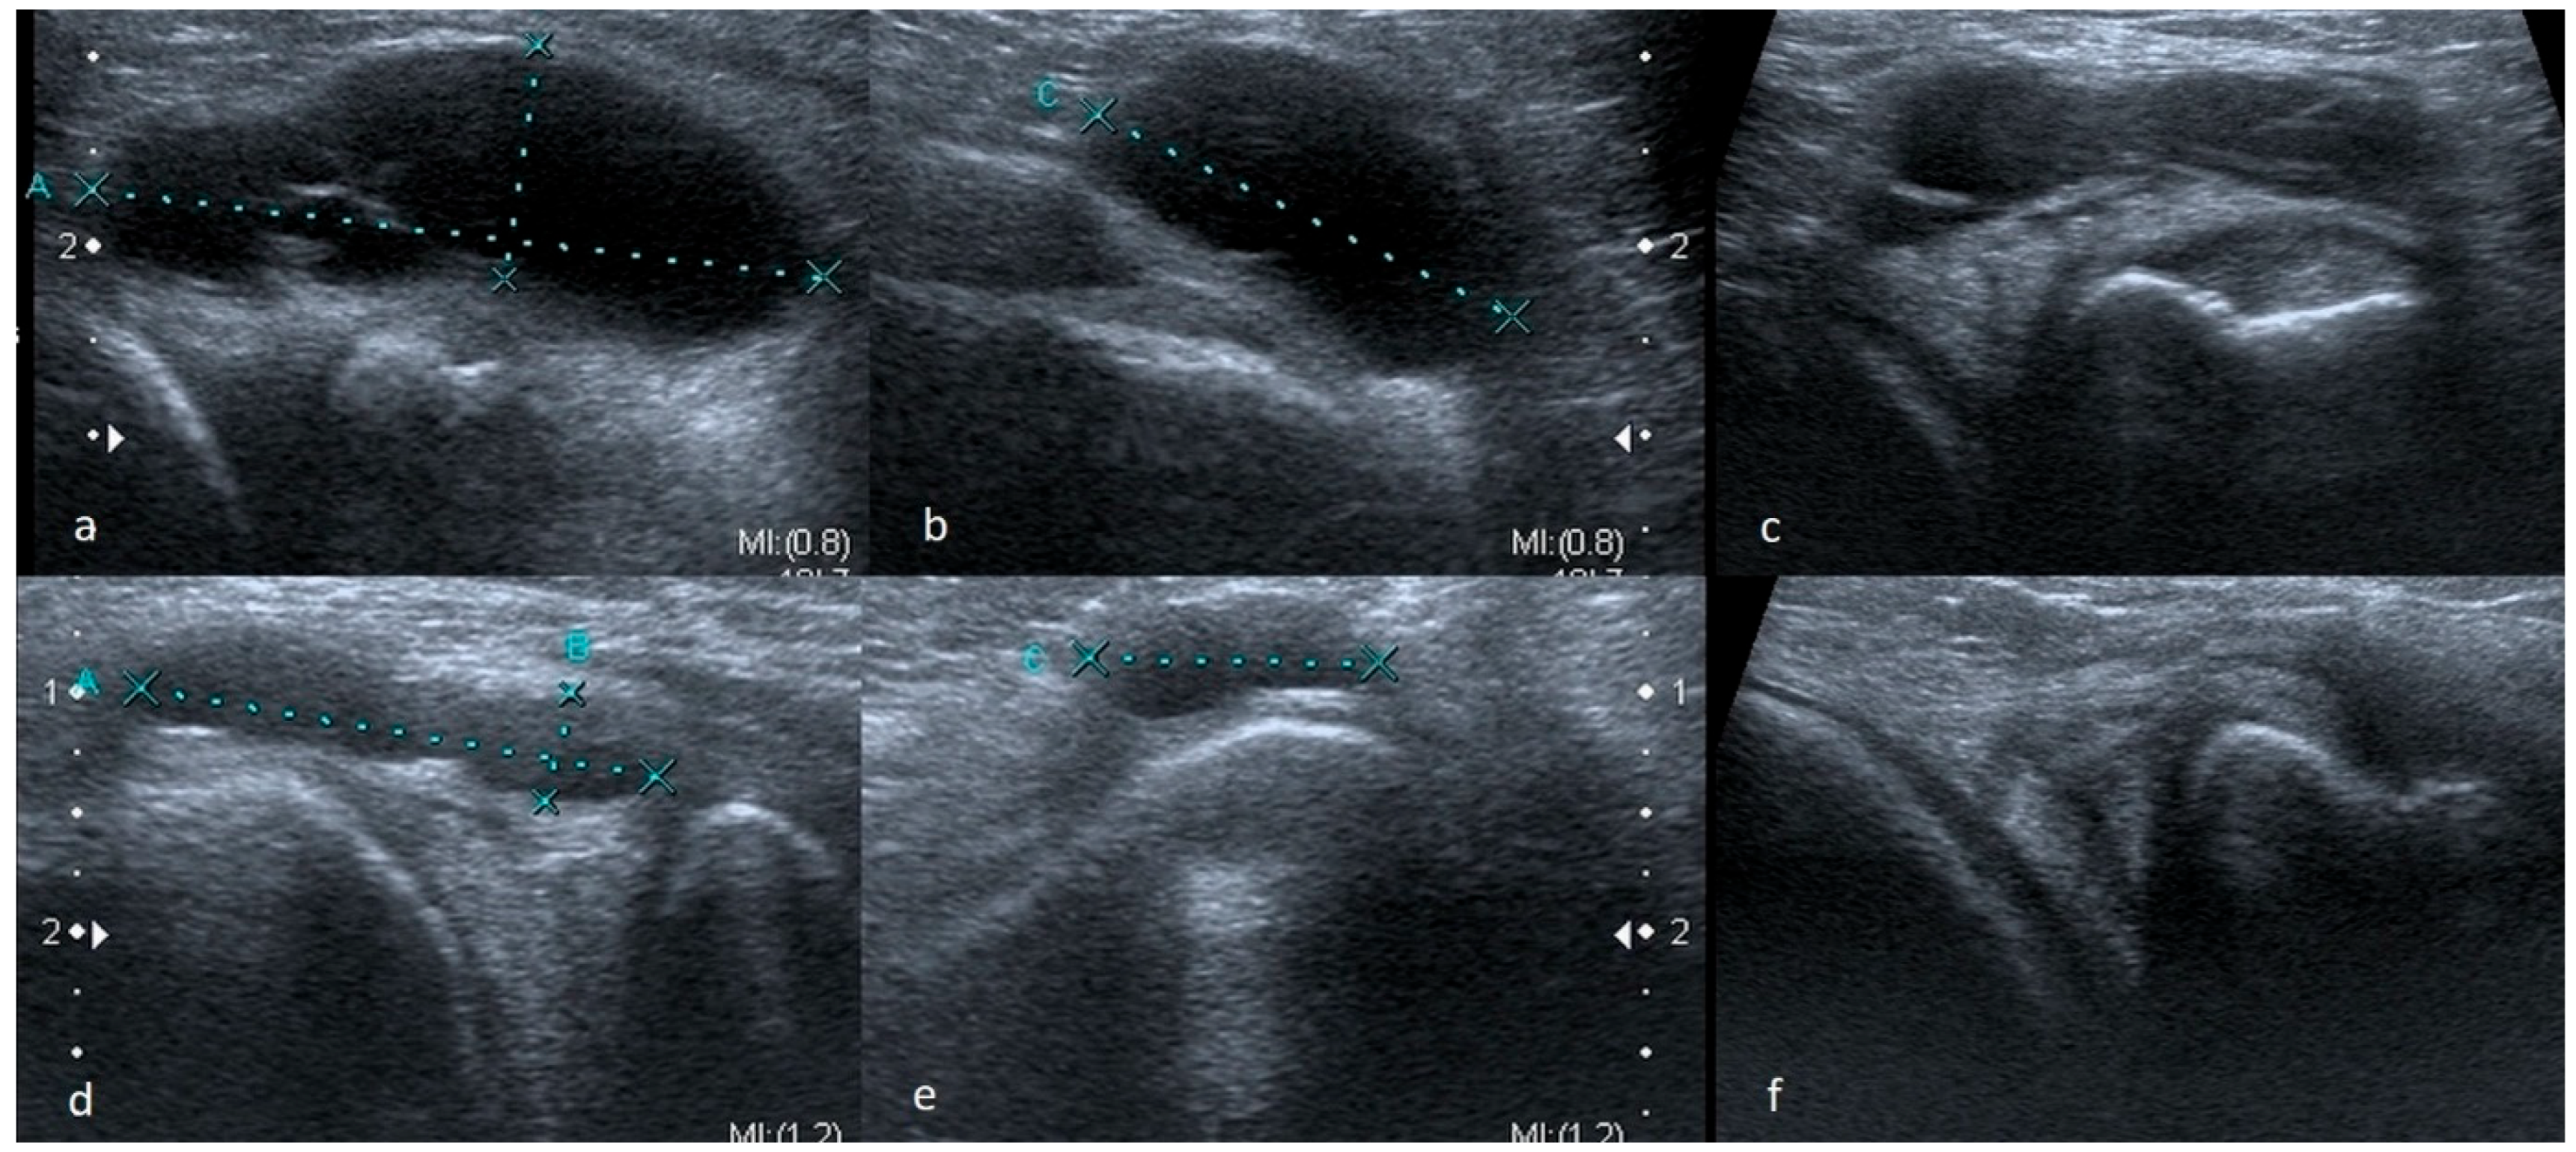

3.1.1. Meniscus Tears

3.1.2. Meniscus Cysts

3.1.3. Bucket-Handle Tears

3.1.4. Meniscal Flap Tears